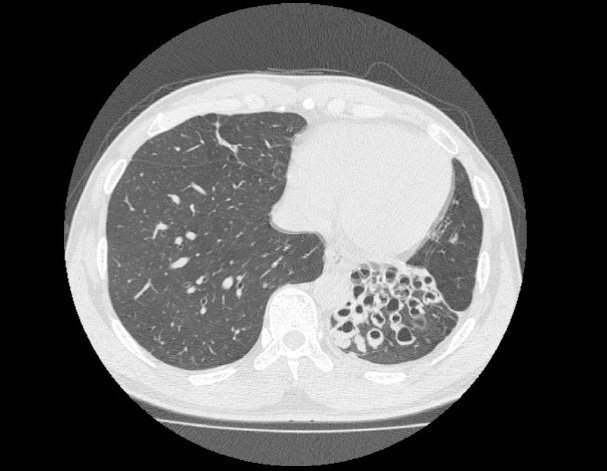

비결핵항산균에 감염된 폐사진

A 72-year-old male was referred to our hospital in August 2001 for his pulmonary M. fortuitum infection. His symptoms were coughing, pyrexia, hemoptysis, general malaise, and insomnia. He had been suffering from these symptoms since 1982, though the intensive anti-mycobacterial chemotherapy such as three-drug (RFP, SM, and INH), twice two-drug (KM and SM and cycloserine and enviomycin) and four-drug (CAM, EB, RFP, and KM) regimens were administered for 26 months from July 1999. His symptoms tentatively improved after chemotherapy, but soon recurred with smear positive sputum. We decided to withdraw all antibacterial agents to treat him with decoction of Ninjinyoueito according to the diagnostics Kampo medical science in September 2001. After this prescription, his subjective symptoms gradually improved, and ten months later his sputum converted to smear negative. Because of recurrence of his general malaise in August 2002, we replaced the Ninjinyoueito by Seishoekkito, based on the Kampo diagnostics. His physical conditions remained good until 2005. In addition, the sputum smear examination maintain the level below +/-. We evaluate that Kampo (Chinese traditional medicine) treatment resulted in favorable response. Though it is not common to prescribe Kampo-medicine for intractable infectious diseases, we believe that Kampo-medicine is effective in some cases associated with host defense mechanisms.

일본에 있는 병원에서 비결핵항산균 환자의 치료 사례 논문입니다. 요지는 다음과 같습니다.

"양약치료 후 일시 호전 되었으나 계속 양성반응이 나타났음. 이후 한약치료로 바꾸기로 하고 처방함. 한약 치료 후 환자의 주관 증상이 호전되고 가래검사에서도 음성으로 호전되었다"